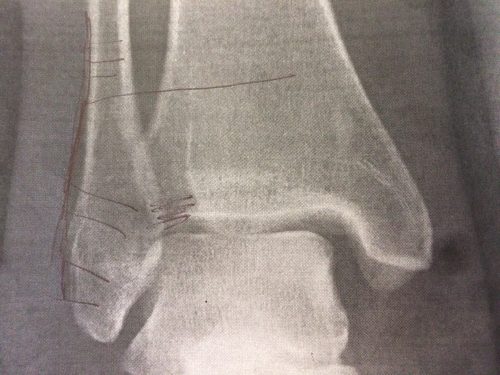

… wird diesmal lange warten müssen. Gestern bin ich von Chris direkt in der Notaufnahme abgesetzt worden. Ein paar Röntgenbilder später war klar, das die Ärzte hier die Meinung der Ärzte in Dänemark teilen. Nach abschwellen des Beines wird nächste Woche irgendwann (wohl eher zum Ende hin, Donnerstag gibt es leckeres Essen) operiert. Platte, ganz viele Schrauben und evtl. eine Stellschraube rein. Erst während der OP wird das ganze Ausmaß zu sehen sein und auch dann entscheidet sich der weitere Verlauf. Aber momentan schaut es nach null Belastung für den Fuß für die nächsten 6 Wochen nach OP aus.

Das „Operationsaufklärungsgespräch“ war heute sehr kurz: „Da Platte, da Schrauben, falls das Band kaputt müssen wir auch da (das Schraffierte) und je nachdem da die Stellschraube (die lange Schraube). Risiken und Nebenwirkungen kennen Sie ja, lesen Sie sich das in Ruhe durch, unterschreiben Sie und falls Fragen sind, fragen“. Sprachs und verschwand wieder …